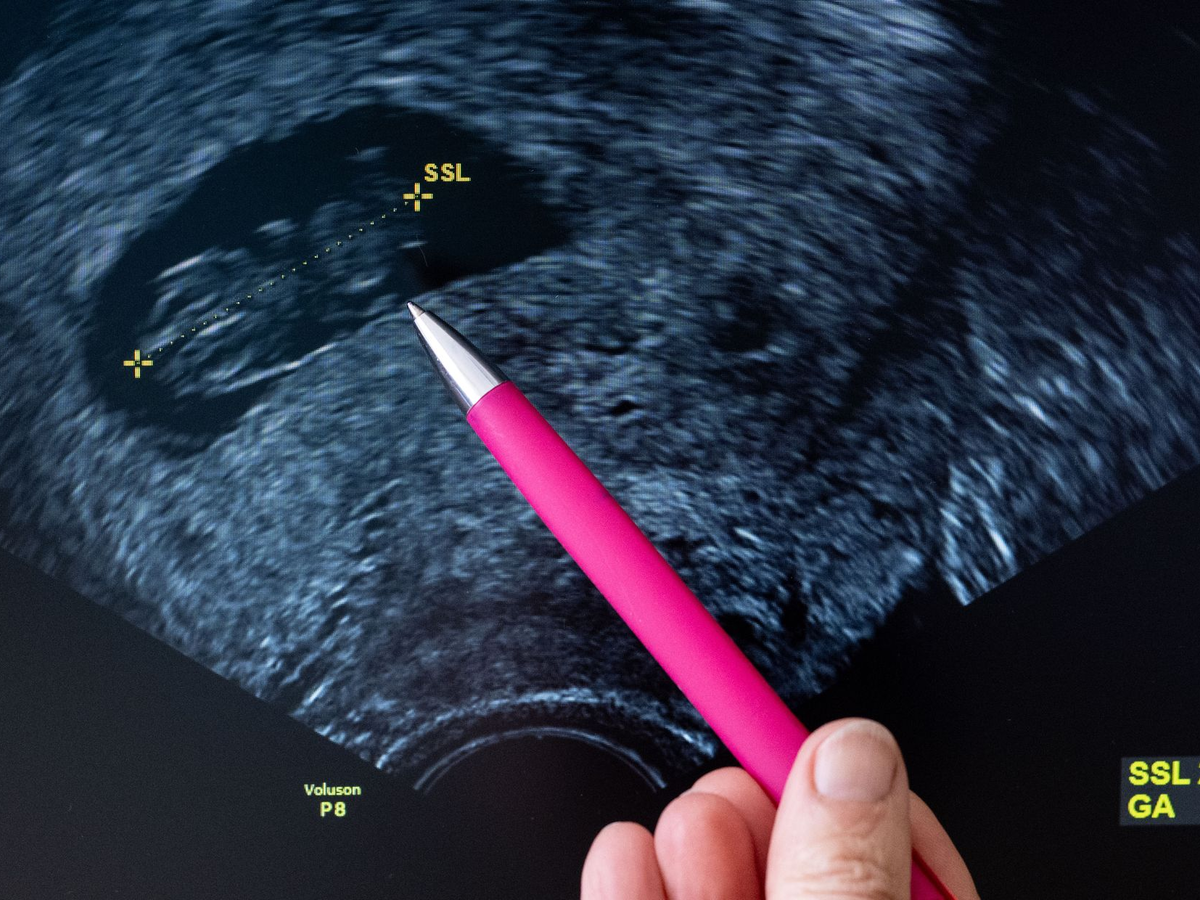

In Paragraf 218 des Strafgesetzbuches steht quasi ein Kompromiss: Eine Abtreibung ist in Deutschland grundsätzlich rechtswidrig, weil laut Grundgesetz das ungeborene Leben geschützt werden muss. Sie ist aber nicht strafbar, wenn sie innerhalb der ersten zwölf Wochen stattfindet und die Frau sich zuvor hat beraten lassen. Ohne Strafe bleibt ein Abbruch auch, wenn medizinische Gründe vorliegen oder wenn er wegen einer Vergewaltigung vorgenommen wird.

Laut Statistischem Bundesamt gab es in Deutschland im Jahr 2023 rund 106.000 gemeldete Schwangerschaftsabbrüche - rund 2,2 Prozent mehr als im Vorjahr. Oft sind junge Frauen betroffen, die meisten im Alter zwischen 18 und 34 Jahre. 96 Prozent der Abtreibungen wurden nach der Beratungsregelung vorgenommen. Medizinische Gründe und Sexualdelikte waren nur in vier Prozent der Fälle Grund für den Abbruch.